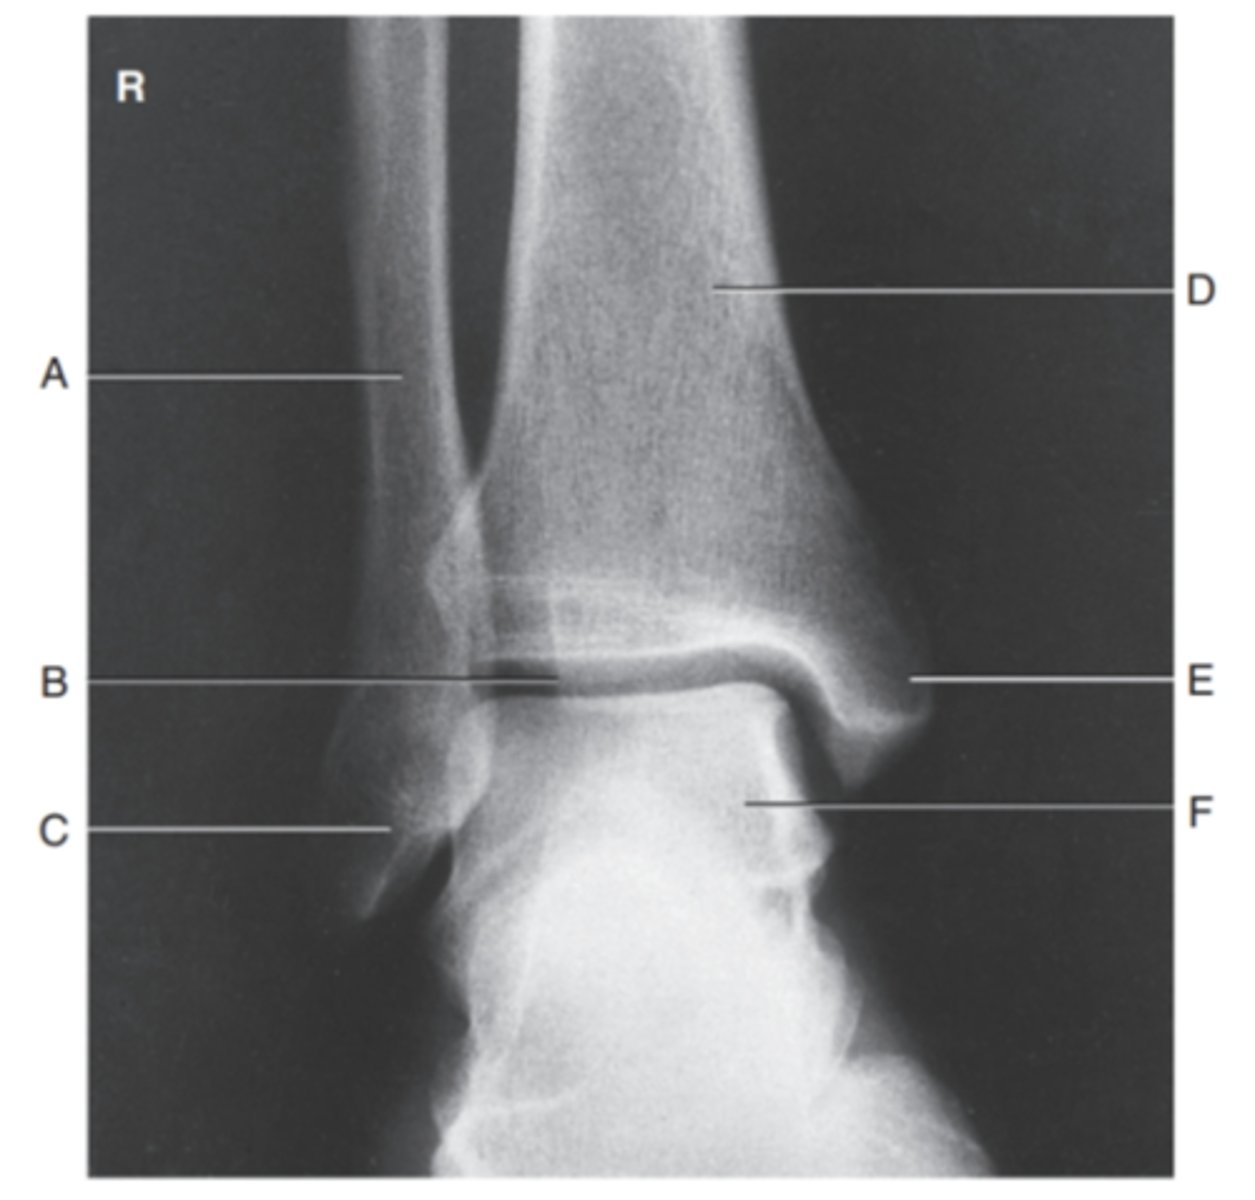

(AP ANKLE) what is A?

fibula

what is B?

tibiotalar joint

what is C?

lateral malleolus

what is D?

tibia

what is E?

medial maleolus

what is F?

talus